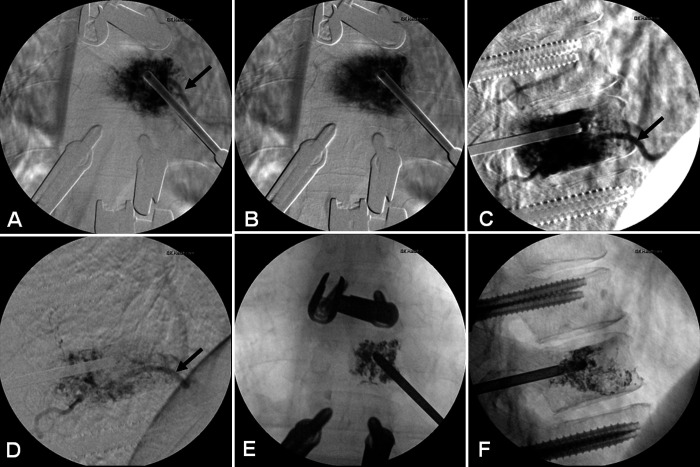

Observations: Here the authors report the first case of a T10 vertebral hemangioma treated with transpedicular Onyx embolization aided by a robotic platform that guided pedicle cannulation and Craig needle placement. An intravenous catheter was attached to the needle and dimethylsulfoxide was infused, followed by Onyx under real-time fluoroscopy. Repeat angiography demonstrated significantly reduced contrast opacification of the vertebral body without compromise of the segmental artery. A T9-11 pedicle screw fixation was performed to optimize long-term stability. The patient's symptoms improved and was stable at the 6-month follow-up.

Lessons: Transpedicular embolization of vertebral hemangiomas can be performed successfully under robotic navigation guidance, avoiding complications seen with the intra-arterial approach and allowing for simultaneous pedicle screw fixation to prevent collapse and delayed kyphotic deformity. During the same procedure, a biopsy specimen can be collected for pathology. This technique can help to alleviate patient symptoms while avoiding complications associated with transarterial embolization or open resection.